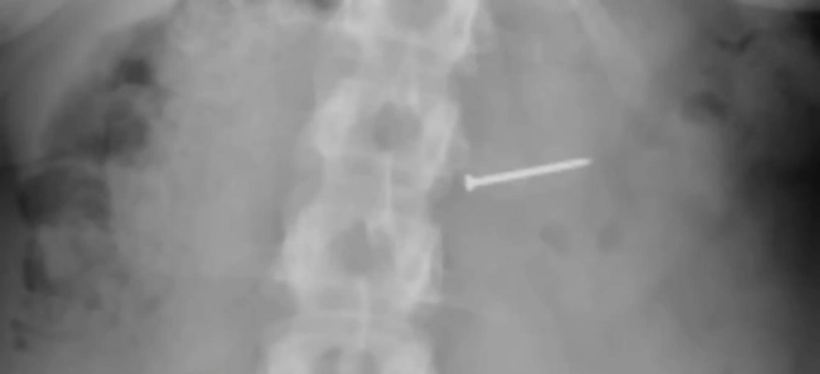

Buckley sau đó đến bệnh viện để chụp X-quang để chắc chắn thứ mình nghẹn có đúng là quả hồ đào hay không nhưng không phải. "Đó là một cái đinh. Vậy là tôi đã nuốt phải một cái đinh", cô nói.

Hình ảnh chụp X quang của Brandy Buckley. Ảnh: NYPost